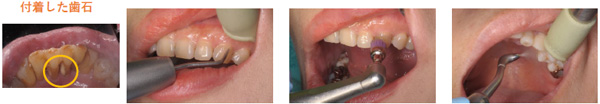

スケーリング(歯垢、歯石除去)

歯の表面に付着した歯垢や歯石を専用の器具、機械を用いて除去します。

スケーリング後歯の表面を研磨することで、再度歯垢や歯石が付着するのを防ぎます。